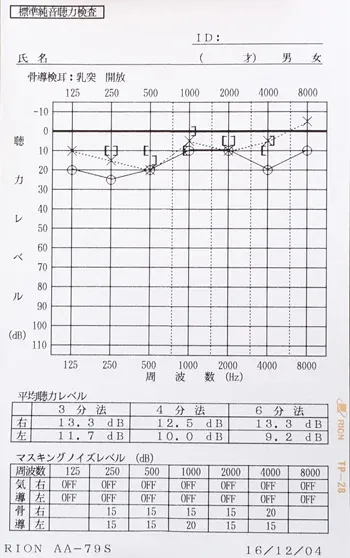

突発性難聴の治療で高圧酸素室に入って治療をした時、耳ぬきがうまくいかずに滲出性中耳炎になってしまいました。痛みは無いので鼓膜に穴をあけるのもとても不安です。滲出性中耳炎は、鍼治療でよくなりますか?